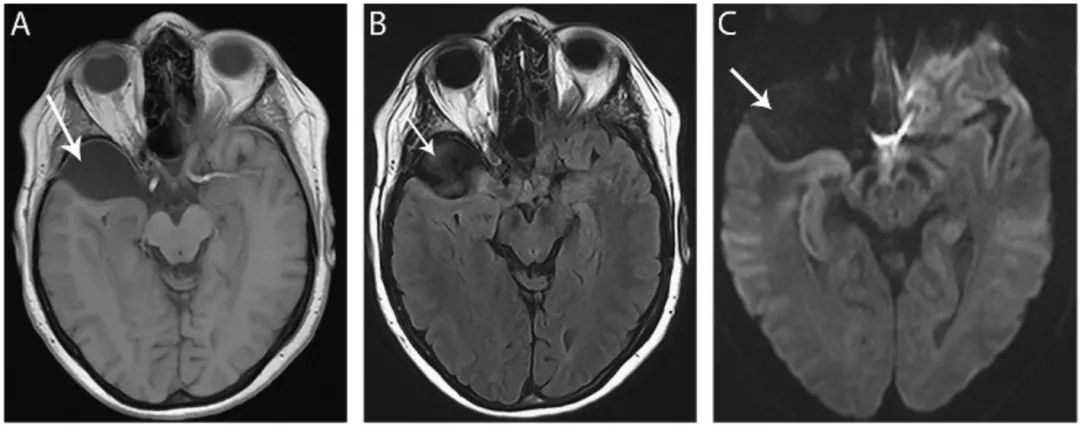

图17 颅中窝蛛网膜囊肿

轴位T1WI(A)、FLAIR(B)和DWI(C)像显示轴外右侧中颅窝前方囊肿(箭头),等CSF信号,右前颞叶可见占位效应。